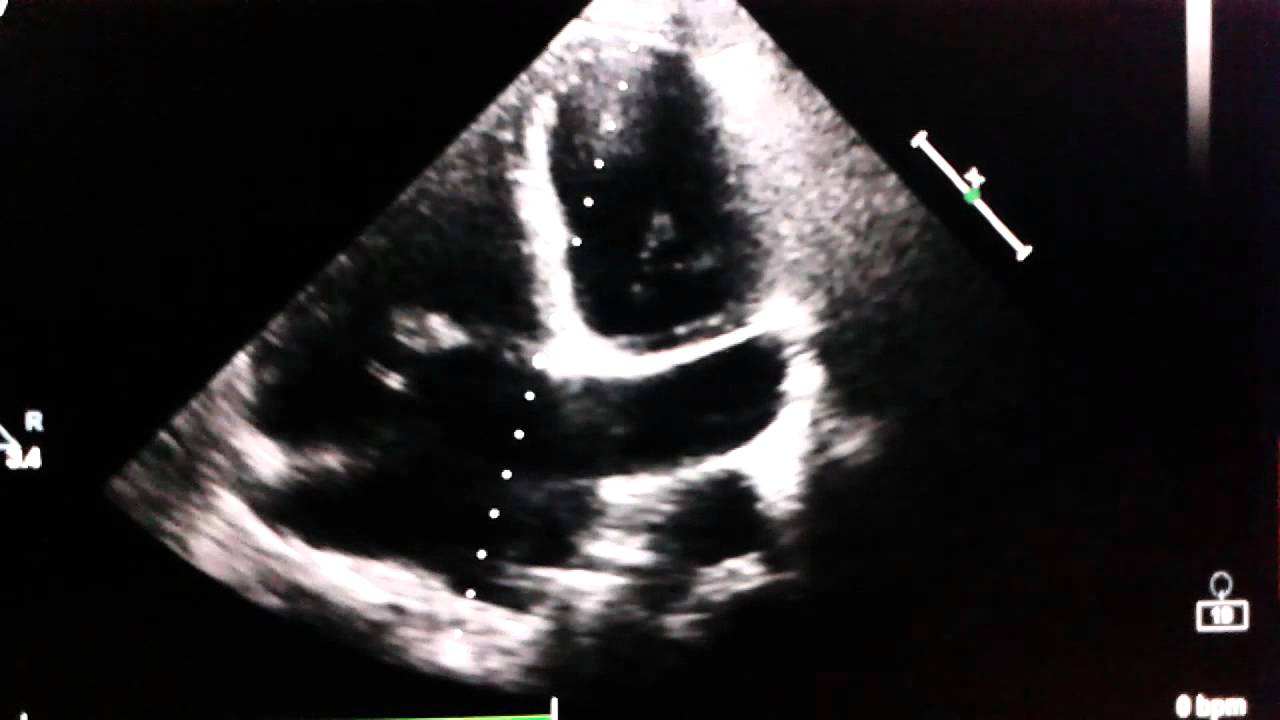

The coronary sinus (cs) can be imaged echocardiographically as a small tubular sonolucency in the posterior atrioventricular groove. Venae cordisminimae (thebesian veins).coronary sinus it's. From recent mouse studies, the origin of this specialised vasculature is from the sinus venosus. It is present in all mammals, including humans. The coronary circulation provides the blood supply to the heart required for the normal muscular function.

2 and 3 dimension transesophageal echocardiography images of the coronary sinus and middle cardiac vein in a patient with severe calcific aortic stenosis.

Echocardiography showing a dilated coronary sinus ...

Echocardiography showing a dilated coronary sinus ... from www.researchgate.net